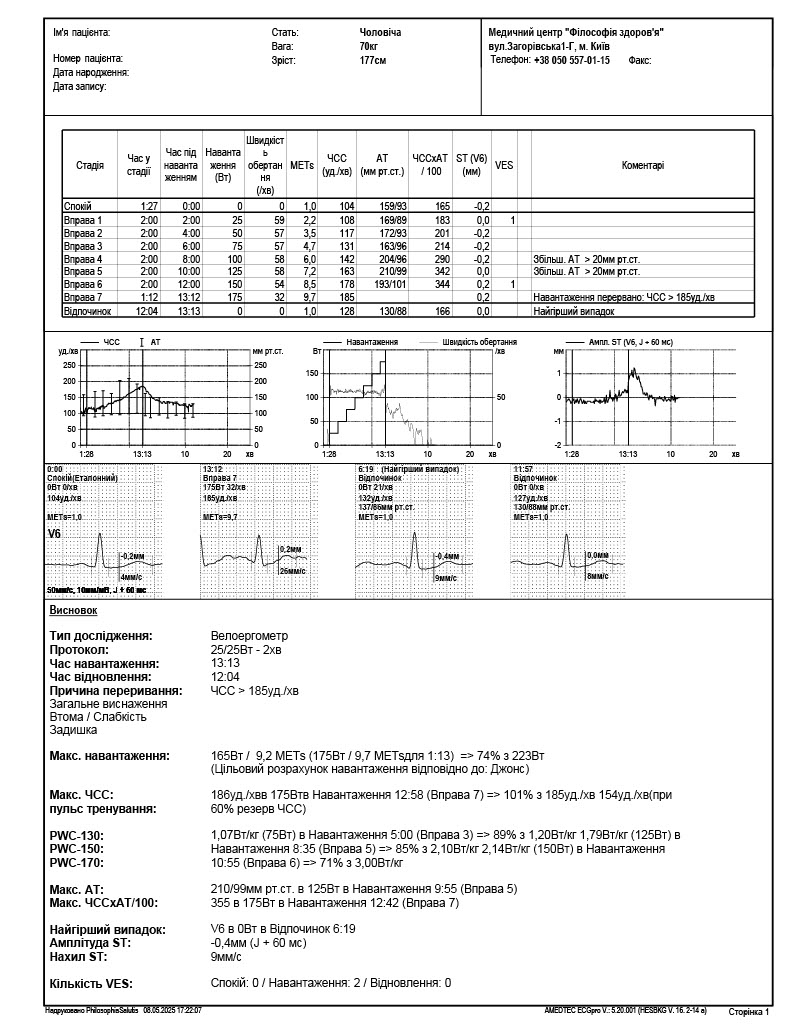

Методика полягає у проведенні електрокардіограми безпосередньо під час дозованого фізичного навантаження у вигляді крутіння педалей на велотренажері. Отримані результати допомагають виявляти навіть ті захворювання, що перебігають приховано або тільки починаються.

У МЦ «Філософія здоров’я» для отримання точних результатів застосовується сучасний велоергометр Ergoselect 4 з 12-ти канальним ЕКГ-реєстратором, автоматичним модулем вимірювання АТ та програмним забезпеченням для стрес-тестів. Інтерпретацію результатів та лікування проводить досвідчений кардіолог, кандидат медичних наук.